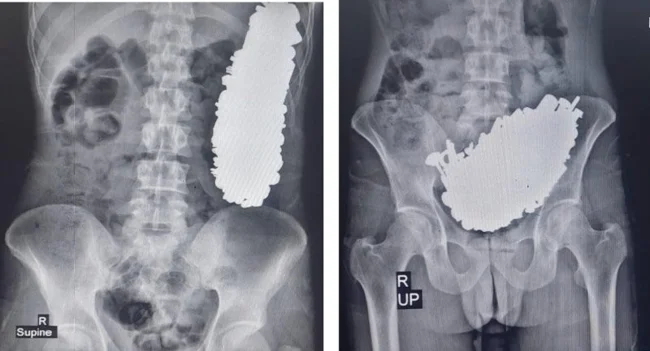

In Iran, doctors removed 452 metal objects from a patient's stomach (2 photos)

Their total weight is almost 3 kg.

A local resident sought medical attention due to chronic stomach pain and frequent vomiting, which prevented him from eating or drinking. Doctors took an X-ray and discovered a large accumulation of metal objects in the patient's stomach, which prevented the body from functioning normally. According to doctors, the man had been swallowing metal objects for at least three months.

As a result, the patient underwent surgery, during which all foreign objects were removed through an incision in the stomach. Among them were, for example, screws, nuts, nails, keys and stones.